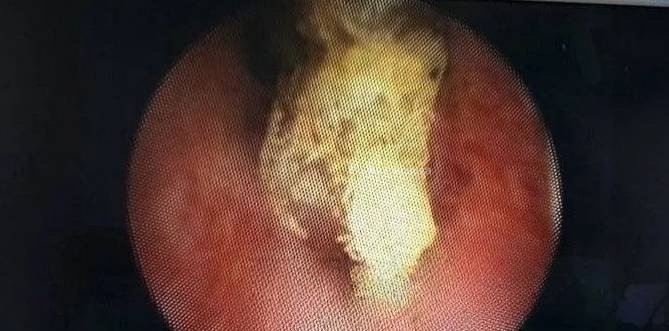

47-летний мужик вызвал скорую и пожаловался на жжение и резкую боль при мочеиспускании — фельдшер заявил, что это не опасно для жизни, и посоветовал обратиться к урологу В ответ пациент признался, что случайно упал на свечу членом засунул в писюн свечку из церкви, чтобы вернуть былую эрекцию — совет он вычитал в интернете Свечку успешно достали в больнице, половой х*й не пострадал Поставил свечку за здравие, буквально 2